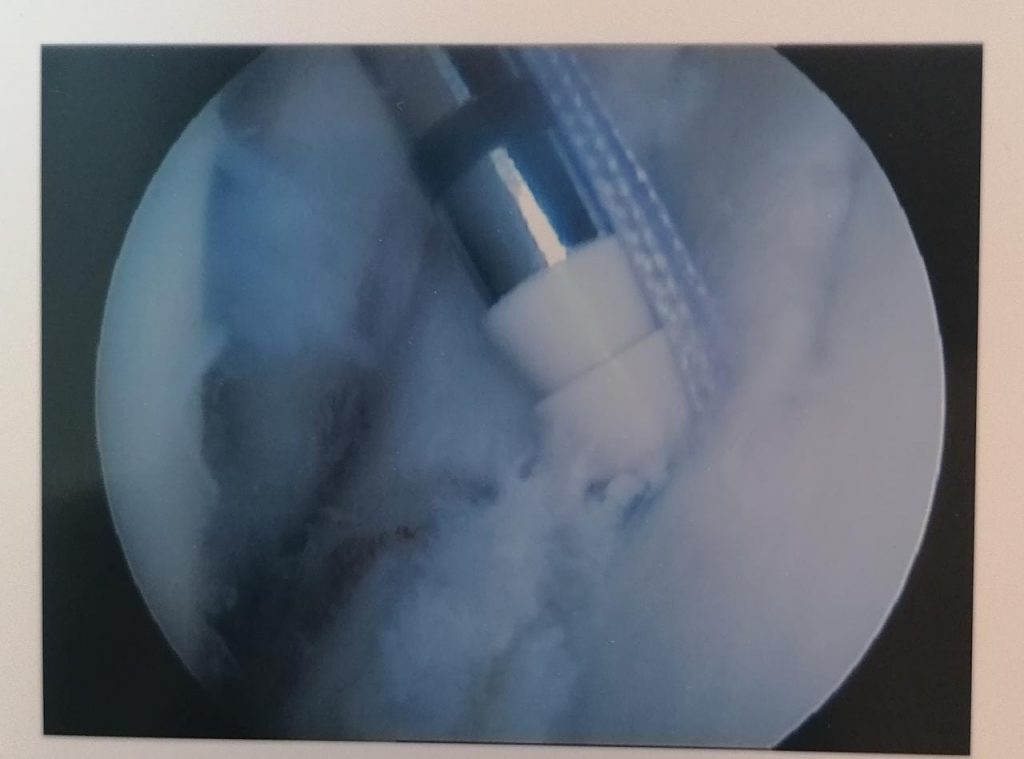

Above are pictures showing the placement of a suture through the edge of the capsule (labrum) to the placement of the anchor as well as the end result. All of this happens through two small incisions.

CALCIFIC TENDONITIS

In some patients the rotator cuff calcifies. This is a painless process. Once the calcium deposit starts to dissolve it becomes very painful. Treatment consists of painkillers, hot packs, steroid injection and, if conservative measures fail, surgery. At the time of surgery the calcific deposit is poked with a needle and the liquefied calcium drains. Usually very effective to manage the pain, though not always instantaneous.